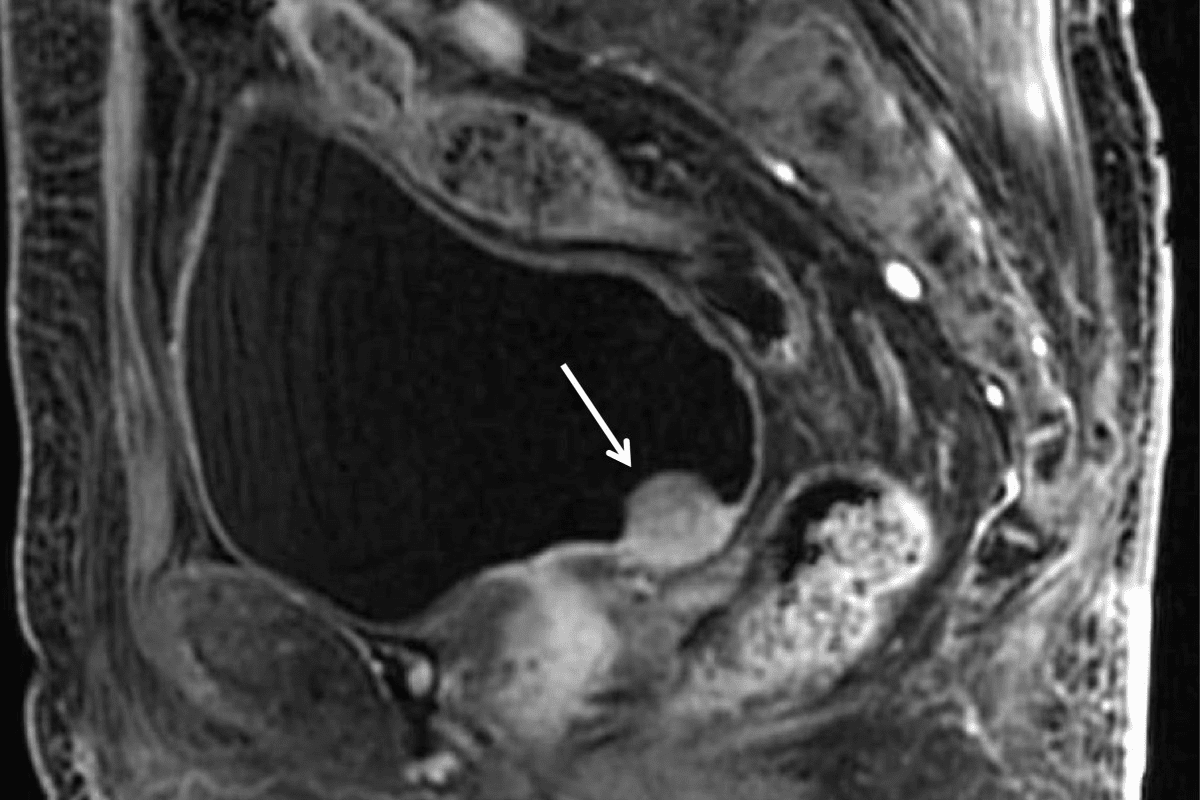

Key characteristics of squamous lung cancer include its tendency to grow in the central airways. It’s also known for necrosis and cavitation. The tumor can block airflow or invade nearby areas.

Imaging Techniques: We often use computed tomography (CT) scans to see the lungs clearly. This helps us spot tumors and understand their size and location. Positron emission tomography (PET) scans help us see if the cancer has spread.

A biopsy is key to confirming squamous lung cancer. We take a tissue sample from the tumor using different methods.

Biopsy Techniques: Bronchoscopy lets us see the airways and get tissue samples from inside the lung. Needle biopsy, guided by images, is another way to get tissue samples.